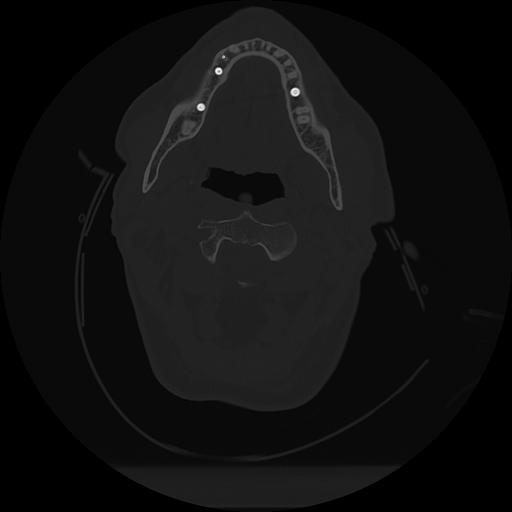

11 HUESO,,Axial,2.0,HUESO,,